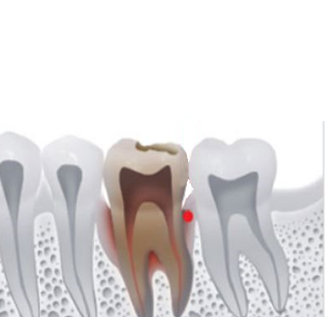

뼈의 양 부족

뼈이식

뼈이식으로 잇몸뼈 형성